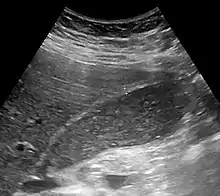

Abdominal ultrasonography showing biliary sludge and gallstones